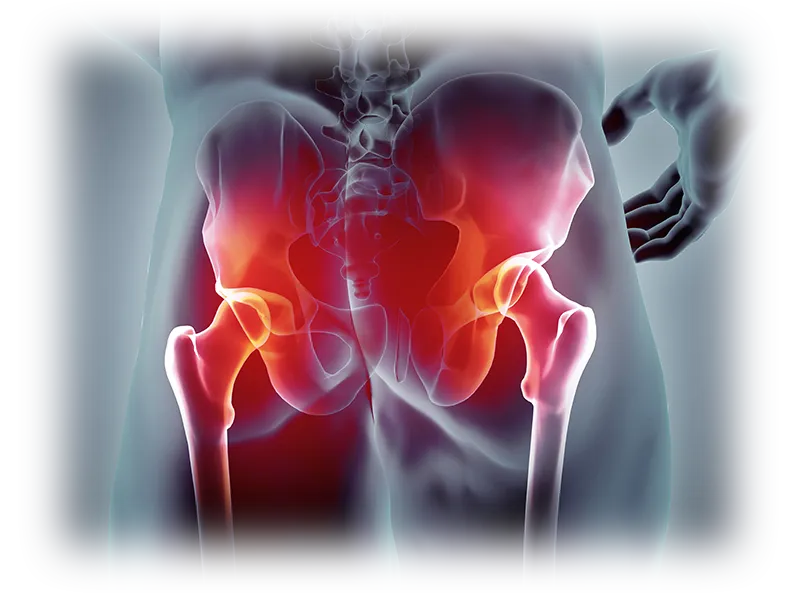

걷기, 앉기, 눕기 등 일상적인 활동에서 가장 많은 에너지를 소모하는 관절은 어디일까요? 바로 "고관절"입니다. 고관절은 골반과 대퇴골(허벅지 뼈)을 연결하며, 몸의 중심부에 자리하여 상당한 체중을 지탱합니다. 척추와 함께 코어 근육의 대부분을 형성하는 고관절은 다양한 움직임을 견딜 수 있는 튼튼하고 안정적인 관절로 알려져 있습니다.

고관절은 골반의 관골구와 대퇴골두를 연결하는 관절입니다. 골반과 다리가 만나는 지점에 위치하며 체중을 지탱하고 다리의 움직임을 가능하게 합니다.

또한 "엉덩이 관절"이라고도 불리는 이 관절은 뼈와 뼈가 연결되어 자유로운 움직임을 가능하게 하는 신체 부위로, 허벅지와 종아리를 포함한 다리 전체를 움직일 수 있도록 돕습니다. 고관절의 움직임과 기능은 걷기, 달리기, 앉기 등과 밀접하게 연관되어 우리 몸의 움직임과 일상 활동에 핵심적인 역할을 수행합니다.